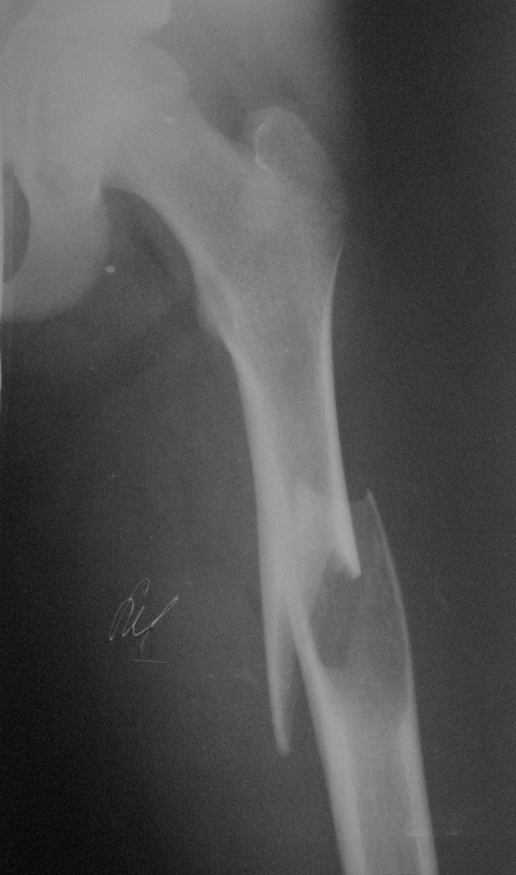

По неотложке в наше отделение попал мальчик 13 л. с патологическим переломом бедра.

Консультирован нашим главным детским ортопедом. Выставлен диагноз: солитарная костная

киста. В профильное отделение переводить мальчика родители не хотят (мне причина не

известна). Рекомендован ЧКОС закрыто без костной пластики. Какие подходы используются в

профильных отделения ваших клиник при даной патологии? Спасибо.